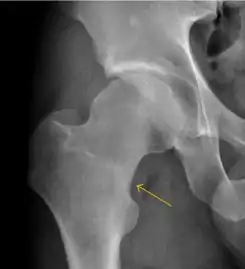

- Slipped capital femoral epiphyses (SCFE)

Slipped capital femoral epiphyses (SCFE) usually affect 11- to 14-year-old adolescents (Figure 4). Radiographs may show widening and irregularity of the physis and posterior inferior displacement of the capital femoral epiphysis. On the AP view Klein’s line, tangent to the lateral aspect of the femoral neck, does not intersect the femoral head indicating that it is displaced. SCFE may compromise the blood supply to the femoral head and cause avascular necrosis, mainly when there is instability between the fragments.[1]

- Figure 4: (a) X-ray of a 10-year-old child with left hip pain. It was considered normal at emergency despite the widening of the left physis (arrow). Two weeks later epiphysiolysis was evident (b). Despite appropriate surgical reduction (c) osteonecrosis developed and femoral head collapsed 1 month later (d).[1]